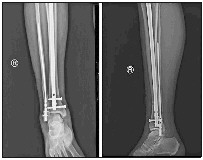

济南市人民医院完成首例腓骨髓内钉手术

本报3月18日讯(记者 亓玉飞 通讯员 通讯员 刘建勇 孙兆云) 近日,济南市人民医院创伤骨科在郭新银副主任的指导下,王星主任医师率领孙兆云副主任医师、李士光主治医师完成该院首例腓骨粉碎性骨折髓内钉内固定手术,这标志着医院骨折髓内钉治疗技术进入更高技术要求的专家级髓内钉阶段。

患者亓某,男,48岁,因摔倒致右小腿疼痛活动受限3小时,于3月2日入院,诊为右胫腓骨粉碎性骨折(远段)。

王星主诊医师团队认真分析患者伤情:按常规治疗方法,可采用切开复位胫腓骨远端钢板内固定手术治疗,但小腿远段软组织覆盖少,筋膜间室空间有限,若在胫腓骨外各放置一块钢板,将大大增加筋膜间室的内容物,造成筋膜室高压或刀口缝合困难。通常此类患者术前需等待2周左右,充分消肿后再手术。而且钢板为偏心型固定,力学稳定性远不如髓内钉的中心型固定。王星主诊医师团队经过讨论,决定采取目前最为先进的髌上入路超远端锁定专家级髓内钉固定胫骨,腓骨远端髓内钉固定腓骨的手术方案。由于腓骨髓内钉省内鲜有应用,创伤骨科申请由外省调来腓骨髓内钉器械,于3月10日顺利完成胫腓骨远端2处骨折2种髓内钉固定手术。术后拍片骨折复位固定良好。

腓骨骨折髓内钉内固定技术的成功开展,标志着该院创伤骨科在髓内钉应用技术应用向远端骨折的更广泛领域扩展,能为更多的病人提供更为微创、牢固、安全、美观的治疗方法。